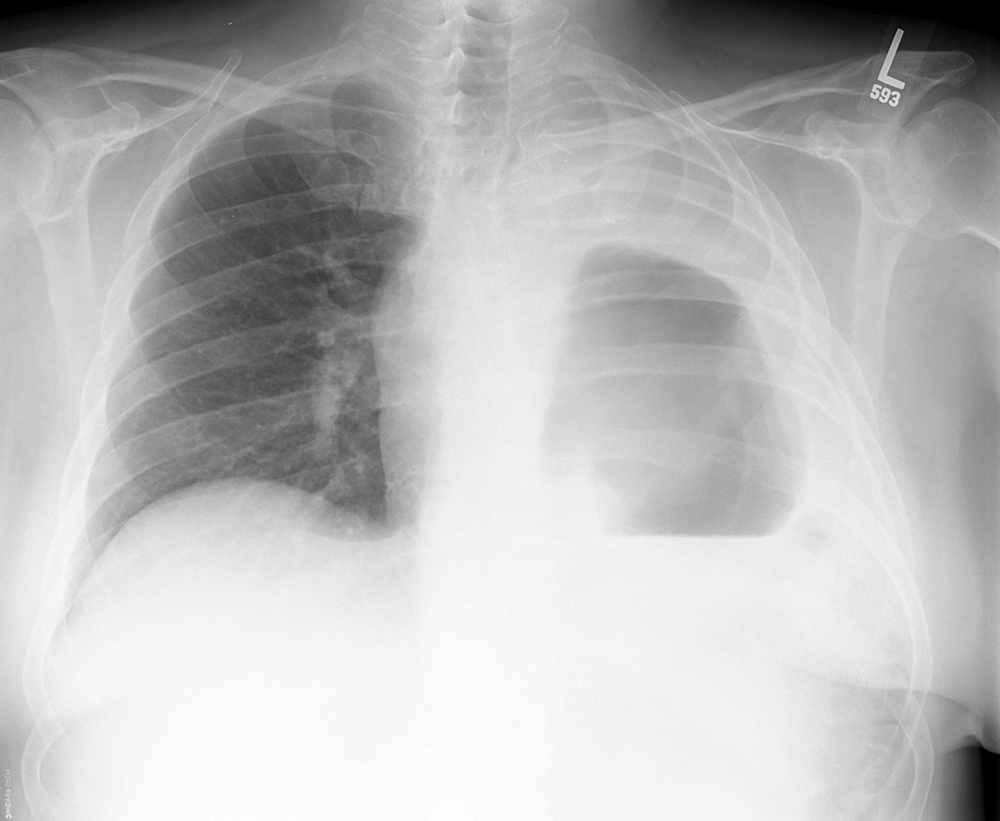

basic case for other abnormal air